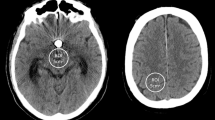

In the standard T2-weighted and T1-weighted sequences, a large area of brain tissue could not be examined due to the artifacts induced by the implanted aneurysm clips. The WARP TSE sequences on the other hand resulted in an impressive reduction in the metal artifacts. Therefore, the assessment of the surrounding brain tissue was considerably improved (Fig. 1). This impression could also be quantified. While the average clip artifact had a volume of 84 ± 63 cm3 and 57 ± 52 cm3 in the T2w and T1w sequences, respectively, with WARP TSE the artifact volume could be reduced to 9 ± 8 cm3 in T2-weighted images and 10 ± 9 cm3 in T1-weighted images (p < 0.001) (Fig. 2). The artifact could be clearly distinguished from the surrounding brain tissue as both raters showed a highly significant correlation in their independently obtained findings (R = 0.91) (Fig. 3a).

Comparison of WARP TSE T2w (b) and T1w (d) sequences with standard TSE T2w (a) and T1w (c) sequences. In the images acquired with the standard sequences, large metal artifacts (solid arrow) after clipping of a right-sided MCA aneurysm diminish the diagnostic quality in both T2w images (a) and in T1w images (c). With the new WARP TSE sequences a substantial reduction of clip-induced metal artifacts (dashed arrow) was achieved (b, d)